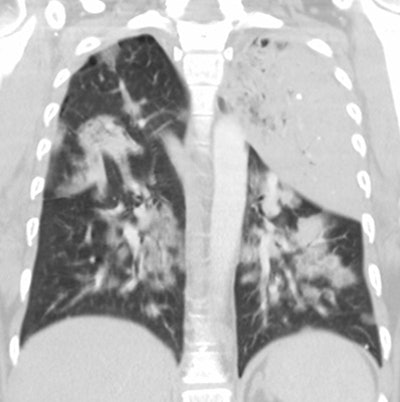

Legionella pneumonia on CT: Bilateral, multilobar airspace consolidations in a patient with Legionella pneumonia. |

The infection usually begins as an area of peripheral patchy airspace disease that progresses to a consolidative pattern. Bilateral involvement occurs in up to 50% of cases. Pleural effusions frequently develop during the course of the illness (up to 50% of cases [2]). Adenopathy and cavitation is rare. The radiographic abnormalities can be slow to clear following initiation of therapy.